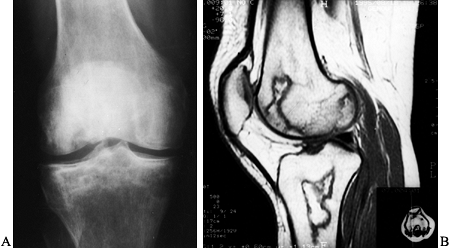

included a measurement of lesion size in both early and late stages.

Symptoms and physical findings were considered important in determining

treatment but were not specifically included as part of the staging (Table 125.4) (Fig. 125.10, Fig. 125.11, Fig. 125.12, Fig. 125.13, Fig. 125.14 and Fig. 125.15). This system of

![]() |

Figure 125.10. Images of a young patient with stage I, steroid-induced osteonecrosis of the right femoral head. A: The plain radiograph is within normal limits. B: The T1-weighted MRI shows a decreased signal intensity in the femoral head, characteristic of osteonecrosis.

|